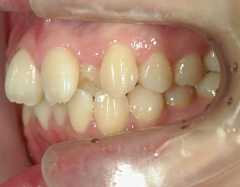

矯正歯科 治療後

no.8_8495_治療後_左.jpgno.8_8495_治療後_正面.jpgno.8_8495_治療後_右.jpg